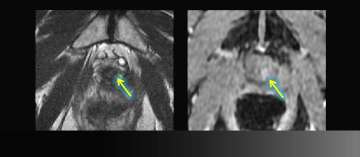

8) Benign Disease (Infertility)

Benign Disease (Infertility)

• Young man presents with infertility (azospermia)

• Workup and medical history otherwise noncontributory

• Muellerian duct remnant in central upper prostate may obstruct ejaculatory ducts

• Left seminal vesicles are atrophic

• Read More >